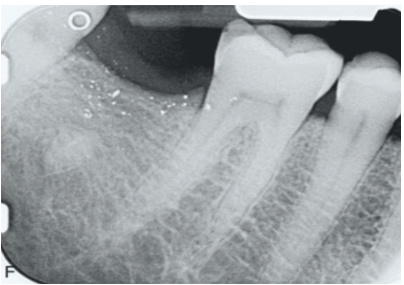

T/F: you can see amalgam tattoo (focal argyrosis) radiographically

true